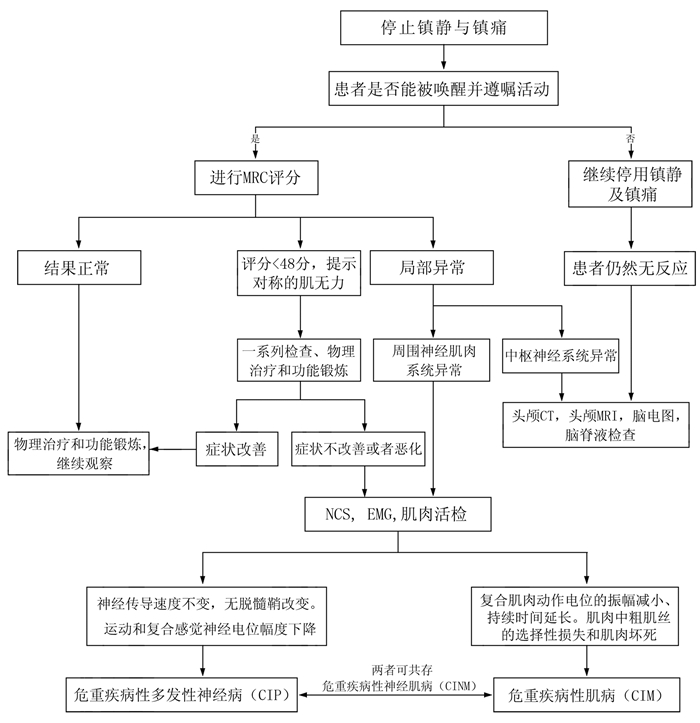

ICU-AW的定义为:重症患者有肌无力的临床表现,但除了本身的危重病外,没有其他明确引起肌无力的疾病[9]。诊断ICU-AW是用英国医学研究理事会(MRC Medical Research Council)评分去评价6对肌群(表 1)的肌力。肌力从0到5共分6级,5级代表正常肌力,见表 2。将6对肌群的肌力相加,总分小于48分诊断肌无力[3]。ICU-AW患者需持续进行MRC评分。如果持续表现肌无力症状,可行肌肉组织活检及电生理检查。如果停用镇静剂后患者昏迷,应进行中枢神经系统检查,如头颅CT,MRI。若检查结果正常,可行肌肉活检及电生理检查。MRC评分亦有局限性,比如特异性不高、需要患者配合等。我们需要更好的床旁工具去评估ICU-AW。当然,亦有其他疾病也能引起肌无力。因此需排除其他引起肌无力的疾病,如吉兰-巴雷综合征、重症肌无力、颈椎疾病、肉毒杆菌中毒、肌萎缩侧索硬化、血卟啉病以及低钾性肌无力相鉴别。ICU-AW诊断流程见图 3。

| NCS(nerve conduction study):神经传导实验;EMG(electromyography):肌电图 图 3 ICU-AW诊断流程图 |